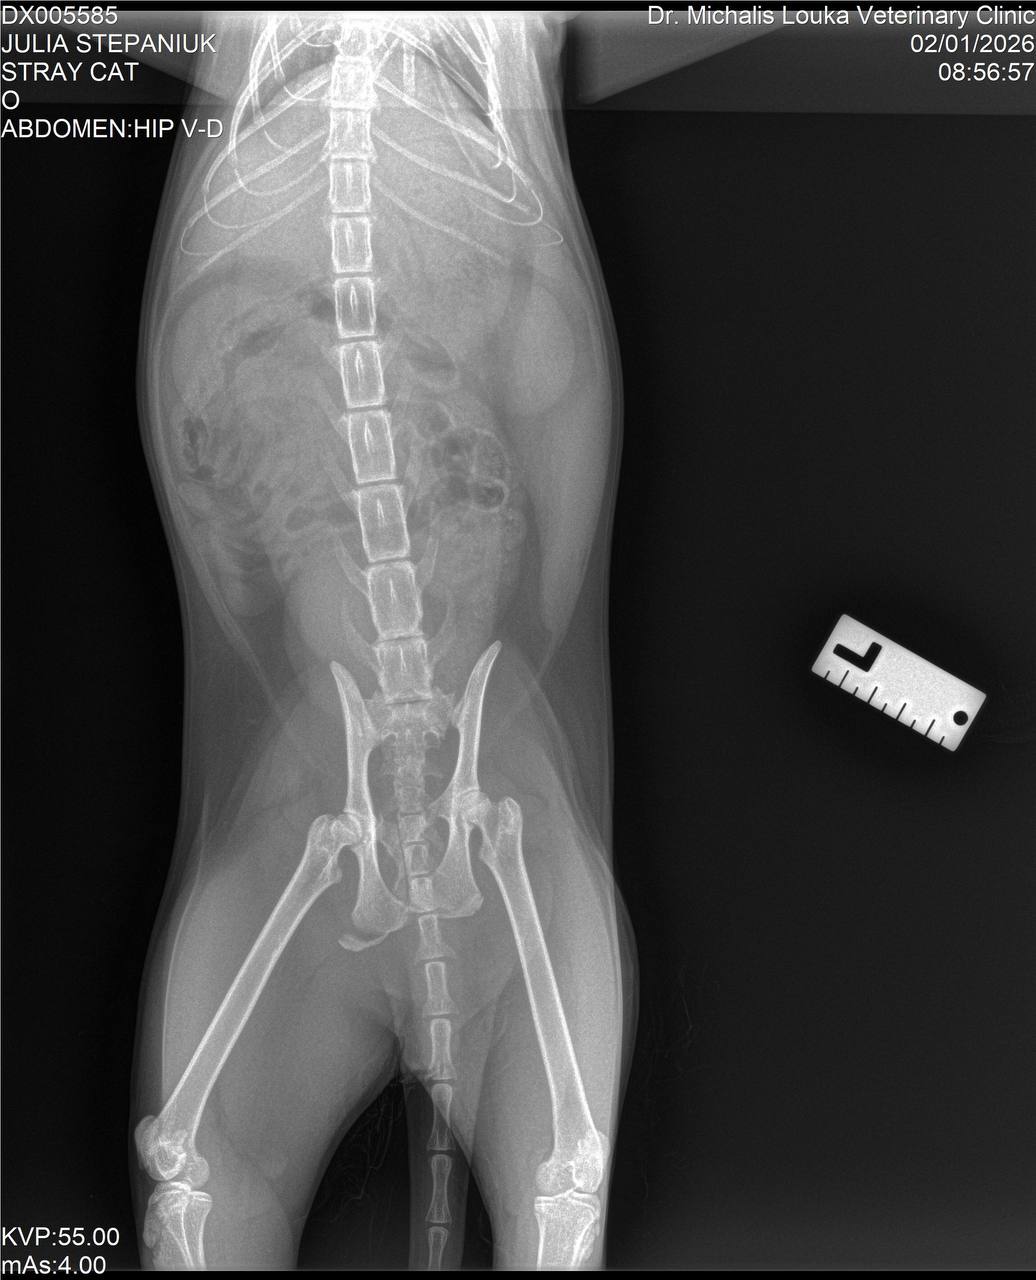

Итак, новости. Сегодня заехала к котику. Его прооперировали, буквально собирали челюсть. Таз тоже переломан, но там операция не нужна. Сейчас стоит трубка в шее до желудка, чтобы кормить.

Кота уже прооперировали — врачи буквально собирали челюсть по кусочкам.

Таз переломан, но, к счастью, операция не требуется.

Боль очень сильная, но чувствительность сохранена — это хороший знак.

Через шею прямо в желудок установлена специальная трубка.